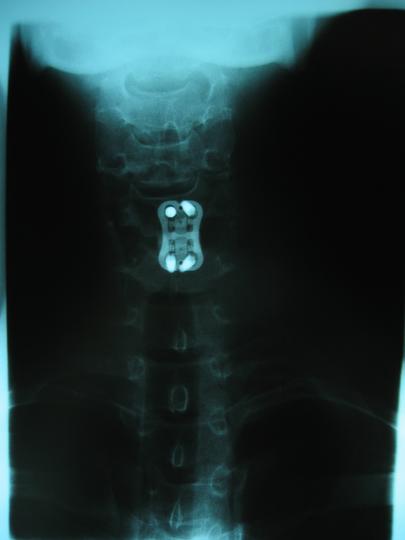

Cervical Fusion, C5/C6; front view

And here I thought I was being paranoid the other day when I looked in the mirror and my head seemed shifted to one side. :/